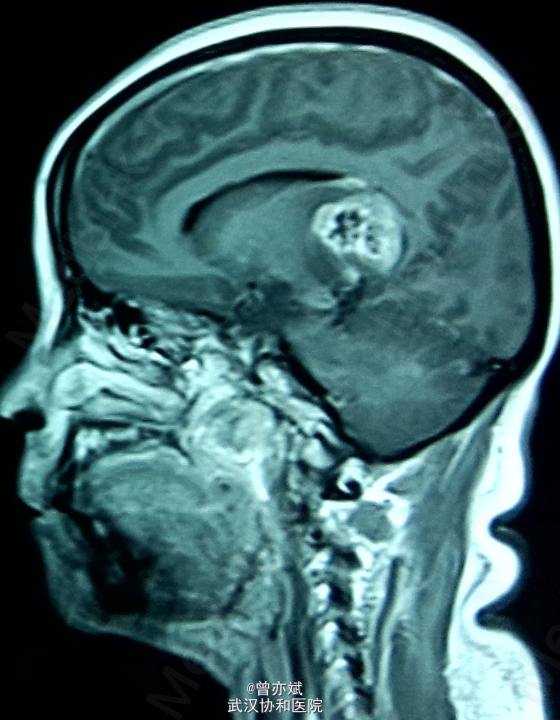

侧脑室占位一例

主诉:间歇性头痛半年余,加重一月 简要现病史:患者半年前无明显诱因出现间歇性头痛,无发热、恶心呕吐、肢体无力、抽搐等症状,近一月来,头痛症状加重,当地医院行MRI提示侧脑室占位。

专科查体神志清楚,双侧瞳孔等大等圆,直径约3mm,光反射灵敏,四肢肌力4级,生理反射村子啊,病理反射未引出。 MRI提示右侧 脑室巨大占位

诊断:右侧侧脑室占位:室管膜瘤? 处理:手术治疗